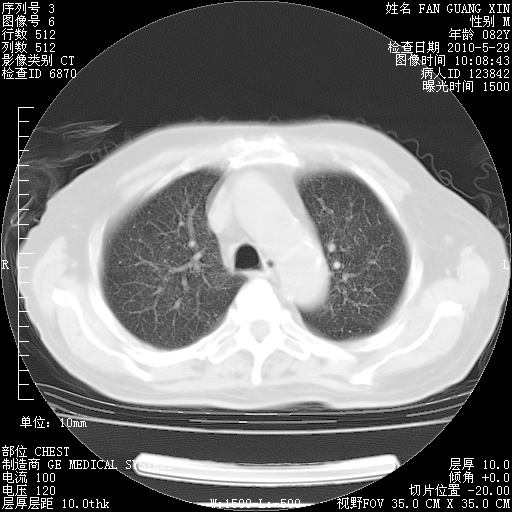

再治疗10天后的肺部CT